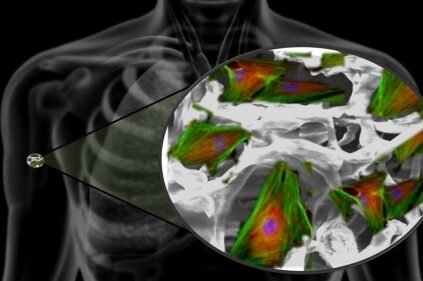

Los nanomateriales, como las nanopartículas de hidroxiapatita y los nanotubos de carbono, son fundamentales en la regeneración ósea. Su alta superficie específica y biocompatibilidad permiten una mejor interacción con las células óseas, promoviendo la formación de nuevo tejido. Además, estos materiales pueden ser funcionalizados con factores de crecimiento para estimular la reparación ósea.

Las nanoestructuras diseñadas para imitar la arquitectura natural del hueso juegan un papel crucial en la ingeniería de tejidos. Por ejemplo, los andamios nanofibrosos replican la matriz extracelular, proporcionando un microambiente adecuado para la migración y proliferación de osteoblastos, esenciales en el papel de la nanotecnología en la ingeniería de tejidos óseos.

La nanotecnología permite el diseño de andamios nanométricos que imitan la estructura del hueso natural, facilitando la adhesión y proliferación de células osteogénicas. Estos materiales mejoran la regeneración ósea al proporcionar soporte mecánico y estímulos bioquímicos precisos.